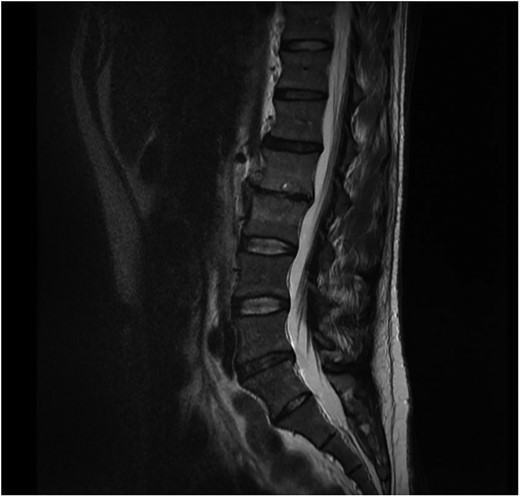

The initial chest and abdominal radiographs were normal but blood tests showed a raised CRP of 244, so broad spectrum antibiotics were started. It was decided that due to the abdominal pain and raised inflammatory markers the patient required a CT abdomen/pelvis which showed para-aortic lymph nodes but no other abnormalities. Testicular lymphatic drainage goes to the para-aortic lymph nodes, so they were examined and had an ultrasound scan which were both normal. Blood cultures grew Staphylococcus aureus and, after discussion with the microbiologist, an MRI spine was performed to rule out osteomyelitis. This showed L2/L3 osteomyelitis, epidural abscess and psoas inflammation (Fig. 1). The microbiologist also advised for a trans-oesophageal echocardiogram to rule out development endocarditis, which was normal. On further questioning, the patient had acupuncture treatment 2 weeks prior to admission for mechanical back pain. The treatment was performed by a trained physiotherapist and involved the insertion of sterile disposable needles into acupoints in the lower back to relieve pain.

Sagital T1 MRI lumbosacral spine. Osteomyelitis in L2 and L3 vertebral bodies, epidural abscess and inflammation of the psoas muscles.